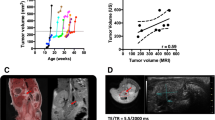

Tumours developed in a heterogeneous manner in the mammary fat pad of 15 rats, with imaging performed at an average tumour volume of 3.6±2.1 cm3 (average ROI slice area for analysis 338±168 mm2) over a wide timeframe post-injection of MNU (median 421 days, range 105–471). One animal simultaneously developed two tumours; both were imaged and analysed. Histology from two tumours was not satisfactorily matched to the imaging plane and was excluded from the analysis. A small sub-cohort (n=4) of the largest tumours was sectioned in two places, into equally sized sections (> 5 mm thick), making 18 matched MR and histological data sets for analysis, from 14 tumours in 13 rats (one animal with two tumours, and two distinct regions each from four tumours).

Representative anatomical and functional images from two tumours are shown in Fig. 1, highlighting the varying contrast and resolution (including a typical ROI for analysis) obtained for each biomarker using the multiparametric MRI approach. The use of different slice thicknesses meant that the MR slice locations were not identical, but in each case were the closest match for the associated histology. Visual matching of the MRI with the corresponding histological sections was good, as demonstrated in Fig. 2 (same tumours as shown in Fig. 1).

Representative anatomical and functional images from two N-methyl-N-nitrosourea-induced rat mammary carcinomas, showing the variation in tumour presentation and typical images from the multiparametric MRI strategy used herein: (a) T2-weighted morphological imaging (T2w), (b) diffusion-weighted imaging (DWI; b=0 mm-2s), (c) ultrashort-echo time imaging (UTE; TE=0.07ms), and (d) magnetisation transfer imaging (MT; flip angle 4°, with MT pulse)